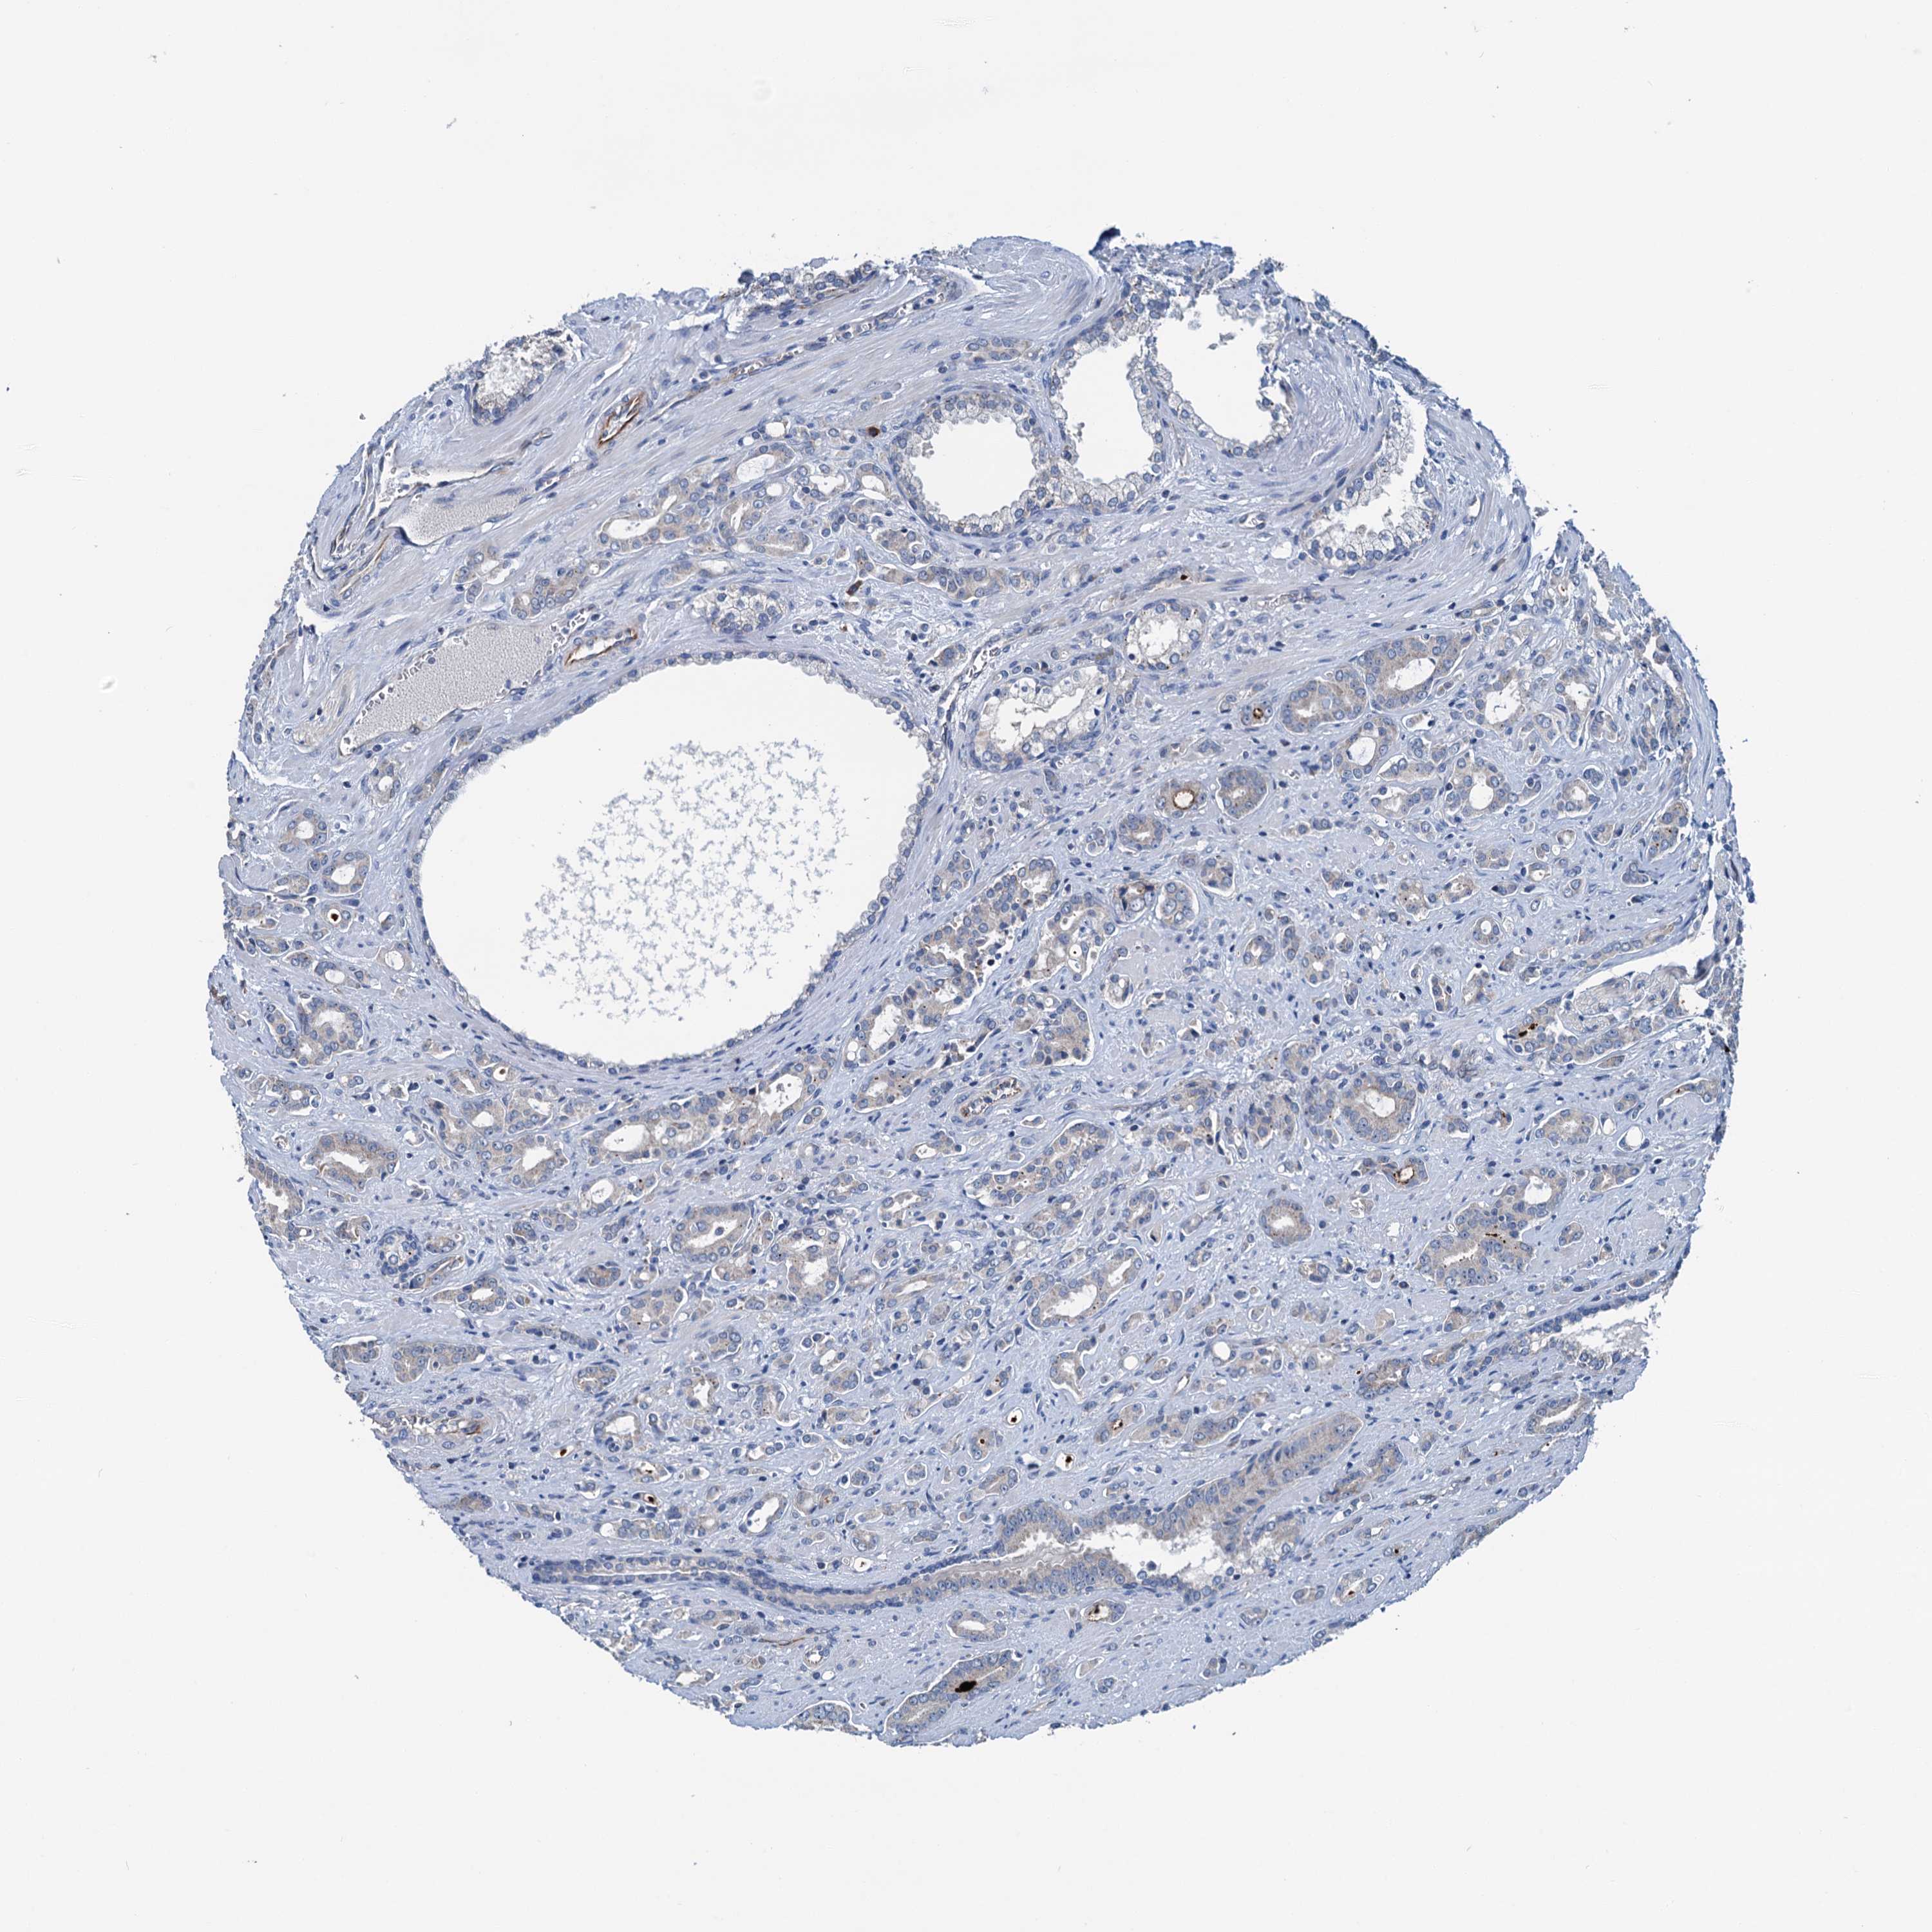

PROSTATE CANCER - Protein expressioni

A mouse-over function shows sample information and annotation data. Click on an image to view it in a full screen mode. Samples can be filtered based on level of antibody staining by selecting one or several of the following categories: high, medium, low and not detected. The assay and annotation is described here.

Note that samples used for immunohistochemistry by the Human Protein Atlas do not correspond to samples in the TCGA dataset.

Antibody stainingi

Antibody staining in the annotated cell types in the current human tissue is reported as not detected, low, medium, or high, based on conventional immunohistochemistry profiling in selected tissues. This score is based on the combination of the staining intensity and fraction of stained cells.

Each image is clickable and will lead to virtual microscopy that enables deeper exploration of all samples and also displays staining intensity scores, fraction scores and subcellular localization as well as patient and tissue information for each sample.

Antibody HPA040867

Staining

High

Medium

Low

Not detected

Intensity

Strong

Moderate

Weak

Negative

Quantity

>75%

75%-25%

<25%

None

Location

Nuclear

Cytoplasmic/membranous

Cytoplasmic/membranous,nuclear

Adenocarcinoma, NOS

Adenocarcinoma, High grade

Adenocarcinoma, Low grade